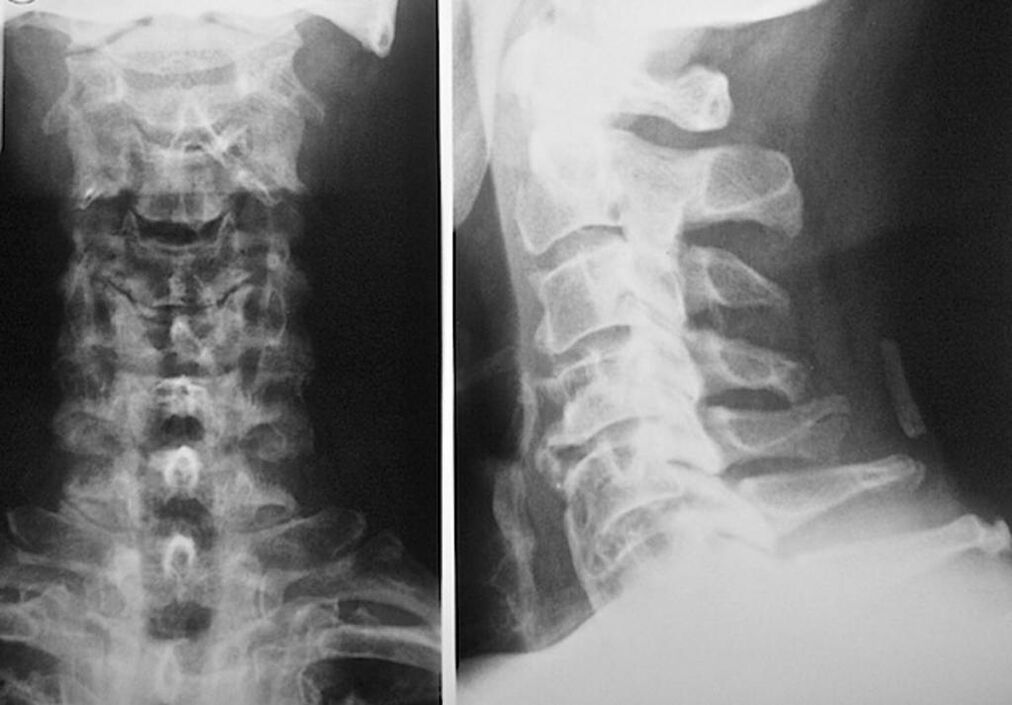

To diagnose and prescribe osteochondrosis of the cervical vertebrae, you must register with a neuropathologist and orthopedic consultation. The neurologist may prescribe treatments for the manifestations of the disease that affect the condition of the nerve endings. This makes sense if the disease is accompanied by radical syndrome. The orthopedist assesses the condition of the spine and diagnoses the presence of other diseases: scoliosis, lordosis, etc.

The following research methods are used to diagnose and accurately assess the condition of intervertebral discs:

- Radiography.

- CT scan.

- Magnetic tomography.

- Ultrasound examination of the cervical vessels.

All are completely safe for health and do not threaten overexposure. Diagnosis of osteochondrosis of the cervical vertebrae, which is treated for the rest of life, can be made after a simple visual examination. This can be easily done by any orthopedist. An exception is the first stage of the disease, when no visible pathologies of the cervical region are detected.